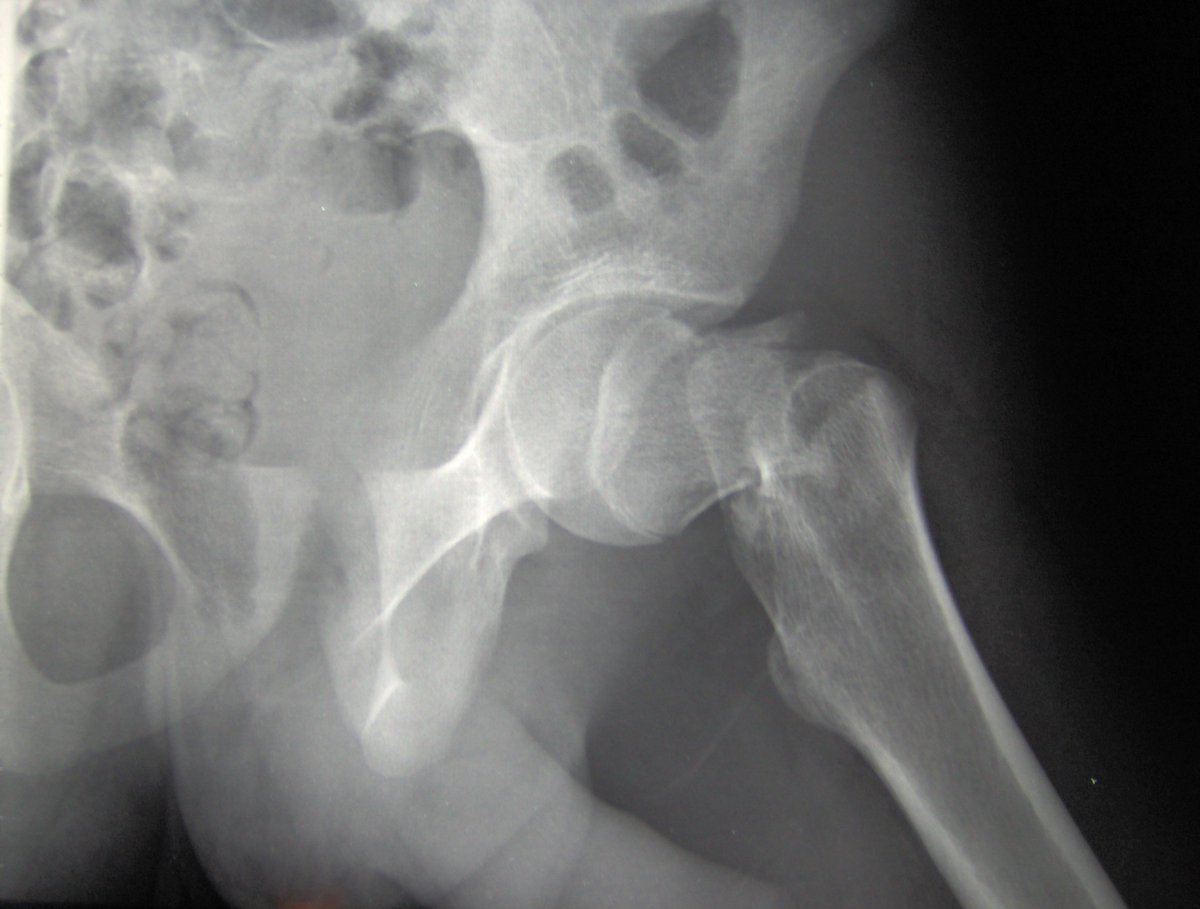

Uncemented hip hemiarthroplasties have higher failure rate and higher mortality compared to cemented. Multiple studies show the same. At what point does it become #negligent to use a fracture inducing implant in bone that has clearly demonstrated it is prone to #fracture?

Cemented or Uncemented Hemiarthroplasty for Femoral Neck Fracture? Data from the Norwegian Hip Fracture Register #CORR #Hip #Registries ow.ly/r36f30oXCHG